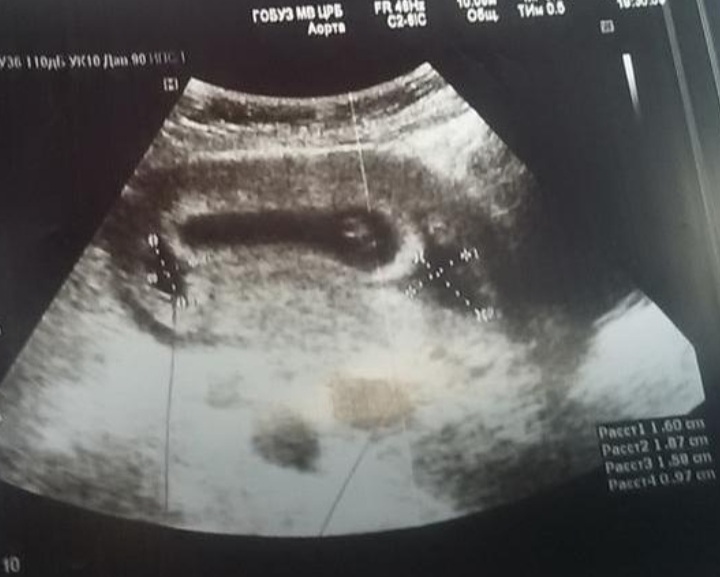

Ретрохориальная гематома . Срок беременности 4-5 недель . . .

Транексам при ретрохориальной . . . обнаружли такую гематому на узи в 12 недель-на 20% от размера плодного пузыря на 15 неделе она прорвалась-кровищи было жуть

Напишу просто на всякий случай то что выписали мне: утрожестан свечи вагинально в дозировке 200 два раза в день (утро и вечер) , аскорутин в таблетках 3 раза в день (рассасыват гематому) , транексам 3 раза в день (кровоостанавливающее и рассасывает гематому) , магний б6 . . .